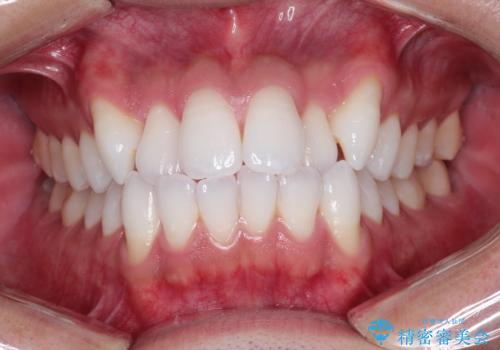

繰り返すプラスチックの欠けを解消。広範囲の修復に適したセラミッククラウン

担当医 河口智英